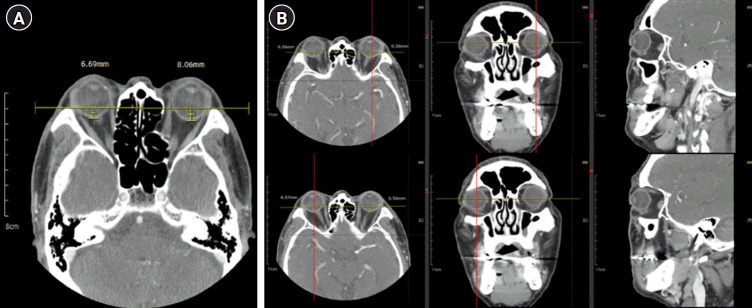

Materials and methods: Sixty-two patients with confirmed TED and resistance to intravenous steroid therapy were treated with RT. Most patients received intravenous methylprednisolone (500 mg weekly for 6 weeks, followed by 250 mg weekly for 6 weeks). After steroid treatment, patients underwent RT with a total dose of 20 Gy delivered in 10 fractions. Clinical parameters were assessed at five time points: initial presentation, post-intravenous steroid therapy, and 1, 6, and 12 months after RT. Inflammation was evaluated using clinical activity score (CAS). Exophthalmos was quantified through posterior scleral distance (PSD) measurements on computed tomography imaging. Statistical analysis involved repeated measures analysis of variance and Cohen's d effect size calculations.

Results: CAS showed significant reduction from baseline (mean, 3.309) to 12 months post-RT (mean, 0.187), with the largest effect size observed between baseline and 12 months (Cohen's d = 10.88). PSD showed worsening after intravenous steroid therapy but gradually improved after RT, approaching baseline values at 12 months. Disease reactivation occurred in only two patients, and three required strabismus correction surgery. Minimal adverse events were reported during follow-up.